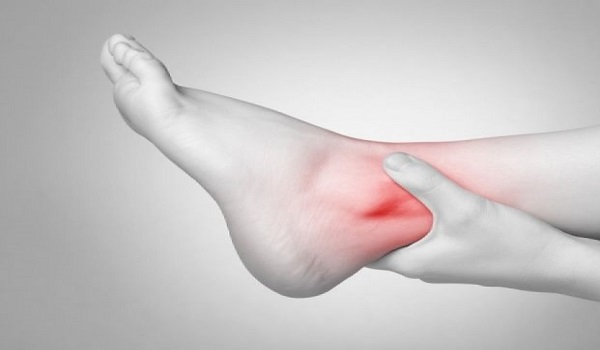

Το ουρικό οξύ είναι μία ουσία που παράγεται στον οργανισμό από το μεταβολισμό των πουρινών. Οι πουρίνες είναι τμήμα των πρωτεϊνών των τροφών που μετατρέπονται σε ουρικό οξύ στον οργανισμό μας και παράγονται είτε από τον ίδιο τον οργανισμό είτε λαμβάνονται μέσω συγκεκριμένων τροφών.

Αν αυξηθεί